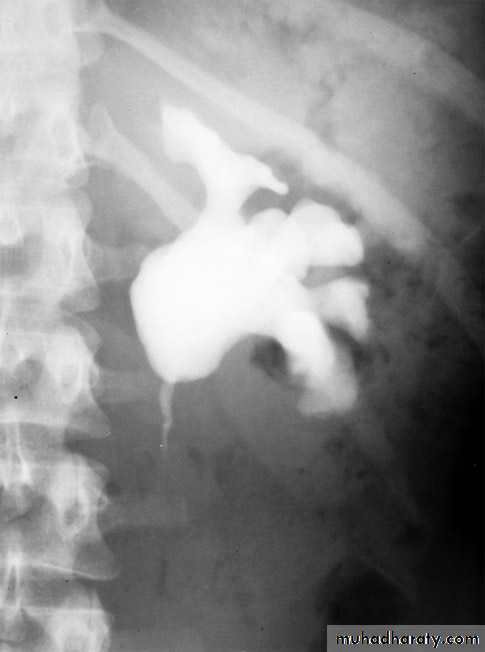

IVU shows

1. The kidneys at low position .

2.Close to the spine with long axis parallel to the spine .

3. Malrotation manifested by medially directed calyces.

4- The renal pelvis and ureters are anterior and lateral in position .